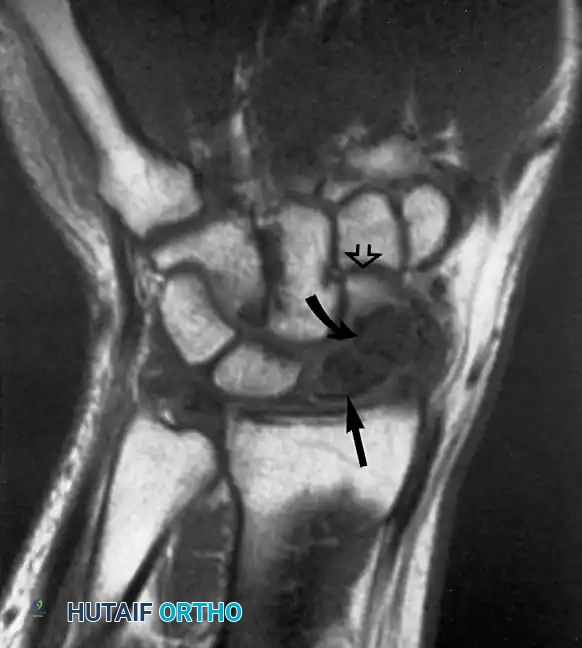

يلعب الرنين المغناطيسي، وخاصة الرنين المغناطيسي المفصلي (الذي يتضمن حقن صبغة داخل المفصل)، دوراً حاسماً في تقييم هذه الإصابة. فهو يكشف بدقة عن التمزقات الجزئية أو الكاملة في الرباط.

صورة رنين مغناطيسي مفصلي تظهر تمزق جزئي في الرباط الجانبي الزندي للكوع